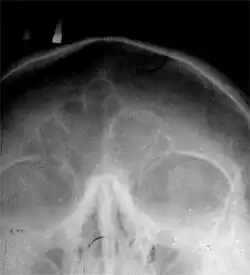

Ло́бная кость (лат. os frontale) — непарная кость мозгового отдела черепа; участвует в образовании переднего отдела свода черепа и передней черепной ямки его основания. Она состоит из четырёх частей: вертикально расположенной чешуи (лат. squama), двух горизонтальных глазничных частей (лат. pars orbitalis) и дугообразной носовой части (лат. pars nasalis)[1].

Наружная поверхность (лат. facies externa) чешуи лобной кости гладкая, выпуклая, имеет в нижней части срединной линии небольшое возвышение, соответствующее остаткам лобного шва, который в детстве разделял лобную кость надвое. С каждой стороны от шва примерно в 3 см от надглазничного края располагается округлое возвышение — лобный бугор (лат. tuber frontalis). Здесь появляется первичная точка окостенения лобной кости. Размер и форма лобных бугров индивидуальны; на детском черепе они выделяются сильнее и иногда могут быть асимметричными, у мужчин бугры больше, крупнее, чем у женщин. Кость здесь имеет гладкую поверхность и покрыта сухожильным шлемом.

Ниже каждого лобного бугра выступает дугообразное возвышение — надбровная дуга (лат. arcus superciliaris); между и немного выше выпуклостей надбровных дуг лобная поверхность имеет вид углублённой площадки — надпереносье, или глабелла (лат. glabella). Обычно у мужчин надбровные дуги также выделяются сильнее, и степень их выстояния зависит от размеров лобных воздухоносных пазух.

Лобная пазуха, sínus frontális, — парная воздухоносная полость, залегающая в передненижних отделах лобной кости между обеими её пластинками. Распространяясь назад, кверху и кнаружи, может иметь самые разные размеры. Лобные пазухи отделяются друг от друга вертикальной тонкой костной перегородкой, которая часто может быть отклонённой в ту или другую сторону; поэтому пазухи редко бывают одинаковыми. Лобные пазухи отсутствуют у новорождённых, обычно они развиваются к 7—8 годам, а максимального размера достигают уже после полового созревания. Размеры пазух резко варьируют, и обычно у мужчин они бывают больше чем у женщин. Пазухи выстланы слизистой оболочкой и сообщаются каждая со средним носовым ходом.